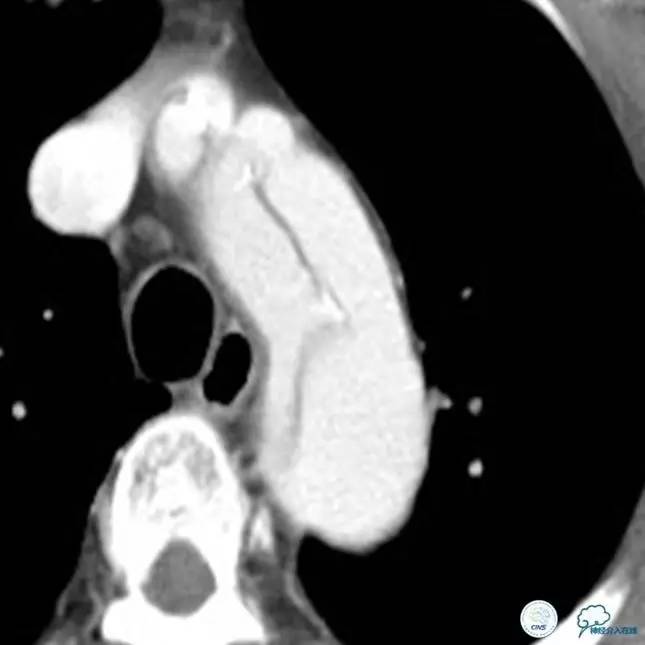

▼主动脉全程CT

诊断:

主动脉夹层 DeBakey Ⅰ型

短暂性脑缺血发作

急性心肌缺血

急性肾功能不全

急性肠系膜动脉缺血